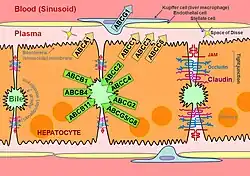

Hepatocytes are organised into plates separated by vascular channels (sinusoids), an arrangement supported by a reticulin (collagen type III) network. The hepatocyte plates are one cell thick in mammals and two cells thick in the chicken. Sinusoids display a discontinuous, fenestrated endothelial cell lining. The endothelial cells have no basement membrane and are separated from the hepatocytes by the space of Disse, which drains lymph into the portal tract lymphatics.

Kupffer cells are scattered between endothelial cells; they are part of the reticuloendothelial system and phagocytose spent erythrocytes. Stellate (Ito) cells store vitamin A and produce extracellular matrix and collagen; they are also distributed amongst endothelial cells but are difficult to visualise by light microscopy.

Schematic of hepatocyte polarization, showing proteins localized to the basolateral and apical surfaces of the hepatocyte, referred to as the sinusoidal and canalicular membranes, respectively

Schematic of hepatocyte polarization, showing proteins localized to the basolateral and apical surfaces of the hepatocyte, referred to as the sinusoidal and canalicular membranes, respectively